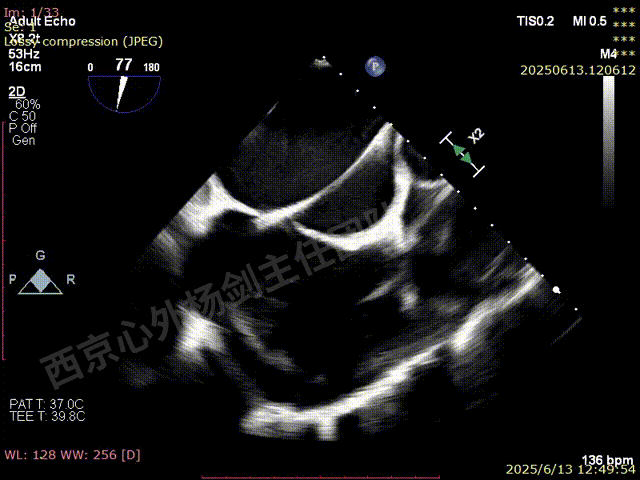

TEER术前超声评估

二尖瓣后叶栓系严重,前叶相对错位,反流束沿2区分布广泛,2偏3区处存在反流。

反流宽度至少23mm,因影像调整困难,考虑实际反流更宽。